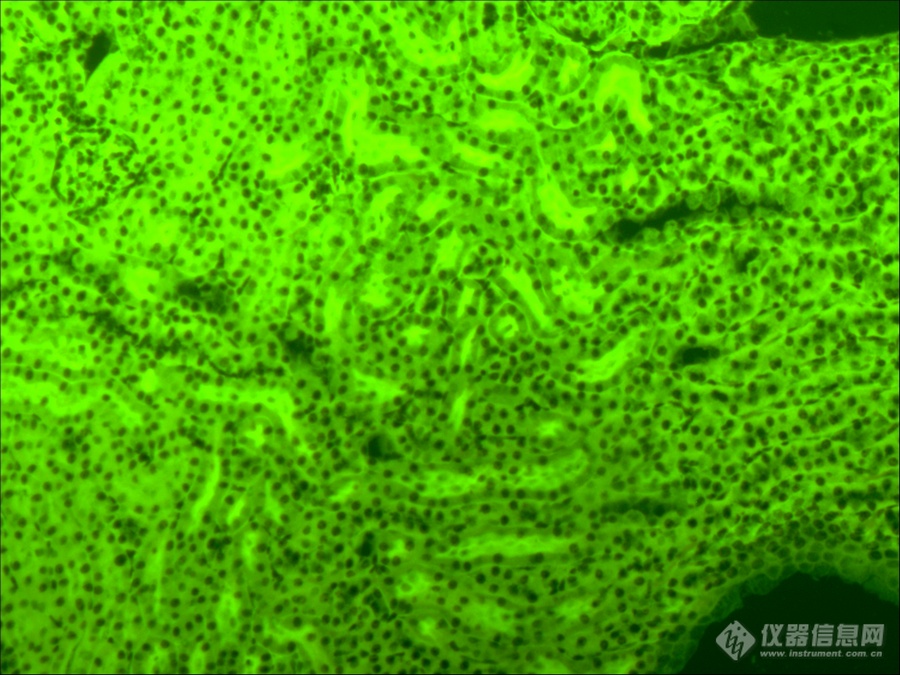

(2)通过检测病毒入侵导致细胞产生的免疫物质或病理形态变化,从而判断病毒种类、分布和数量。正常细胞在面对病毒入侵时,会发生免疫反应,产生的免疫物质就可作为荧光染料标记的结合物,通过荧光显微镜对免疫荧光信号进行观测从而做出检测判断,这种通过对免疫蛋白进行标记的方式也称之为免疫荧光(IF),这种方式在临床上常见的应用有呼吸道七联检或九联检。

呼吸道七联检免疫荧光,MF31拍摄(绿色为病毒反应)